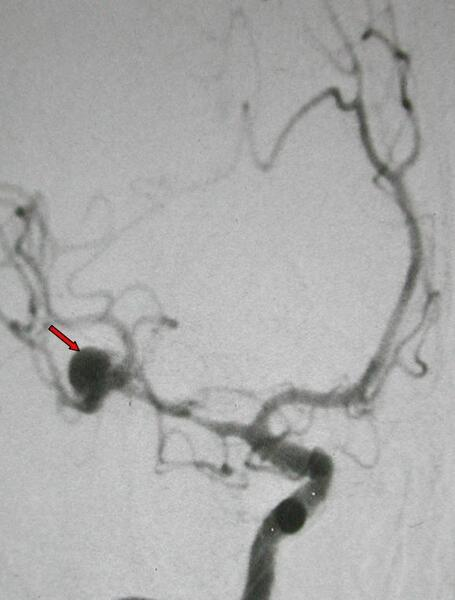

肾外表现包括肝脏、胰腺、脾脏、蛛网膜囊肿等,肝囊肿最常见的肾外表现,部分肝囊肿可以导致肝脏破裂,出血,感染等风险。而颅内动脉瘤危害最大,一旦破裂可导致蛛网膜下腔出血或颅内出血,出现剧烈头痛等,研究显示常染色体显性遗传的多囊肾动脉瘤的发生率高达 12.4%,所以有多囊肾的患者都需要做颅内血管的检查。

▲ 多囊肾动脉瘤,如图所示